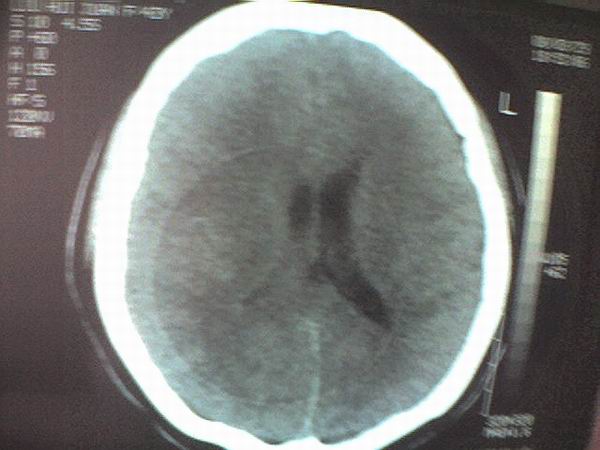

女 43岁 头痛恶心呕吐两天

手机照的,不是太清楚。

右侧大脑镰硬膜下出血

1、右侧大脑镰硬膜下出血2、机器伪影太重,该修修。